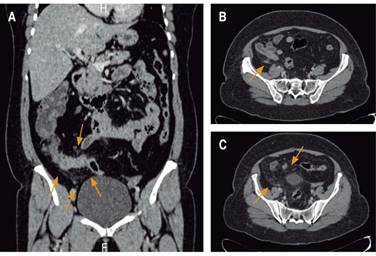

A la exploración física se encontró con dolor en el abdomen a la palpación profunda en fosa iliaca derecha; punto de McBurney; signo de obturador, psoas y signo de Von Blumberg positivos; puntos ureterales derechos superior y medio; Giordano derecho positivo. Se solicitaron exámenes de laboratorio (biometría hemática, química sanguínea y reactantes de fase aguda) que mostraron como únicos hallazgos importantes leucocitosis a expensas de neutrofilia en 94% y proteína C reactiva en 4.3 mg/dl. Como estudios complementarios del cuadro de dolor abdominal se realizó tomografía computarizada de abdomen simple y con contraste intravenoso (Figura 1), sin identificación de apéndice cecal y con cambios inflamatorios en grasa pericolónica del lado derecho, reportado por el Servicio de Radiología.

Figura 1: A) Corte coronal, en el que se visualiza realce periférico de la mucosa de asas de intestino delgado y los cambios por estriación de la grasa adyacente. B) Tomografía de abdomen corte axial, posterior a la administración de material de contraste, se identifica aumento en la densidad de la grasa mesentérica en topografía de la fosa iliaca derecha adyacente al ciego, así como realce periférico de la mucosa del mismo, lo cual se asocia a múltiples imágenes de aspecto nodular correspondientes con ganglios de características inflamatorias. C) Cambios inflamatorios de la grasa mesentérica que se extiende hacia el hueso pélvico.